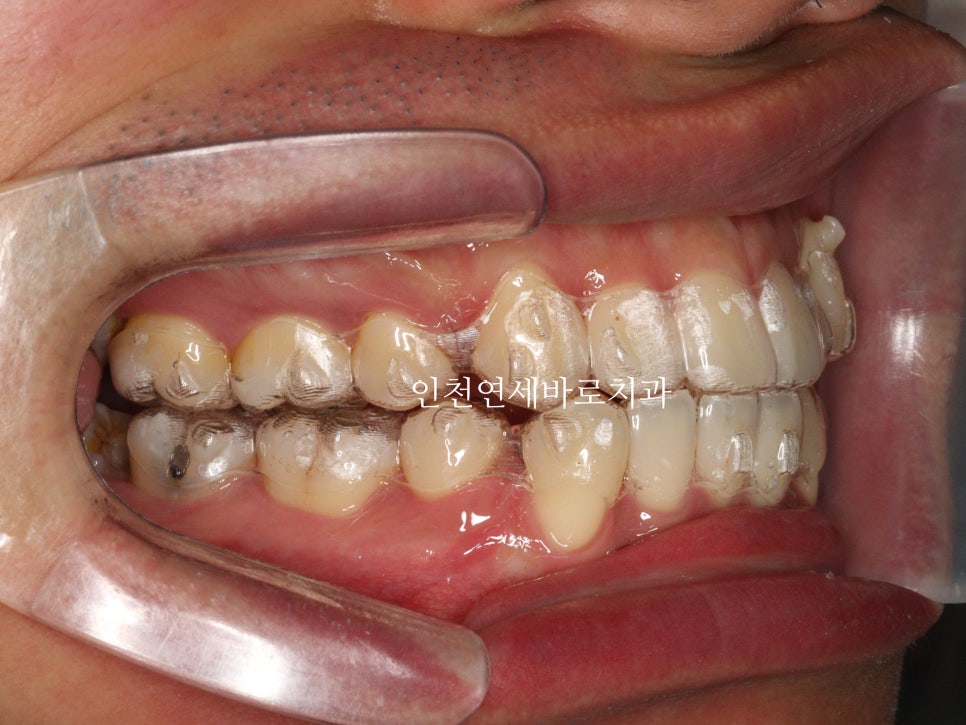

약 7개월이 지난 후의 사진인데 벌써 많은 양의 덧니가 해결되었네요

약 1년 4개월이 지난 모습입니다.

첫번째 세트가 마무리 되었고, 원래의 계획이라면 마무리도 가능한 시점입니다.

하지만 중심선과 교합 등 아주 미세한 부분들이 아쉬워 재제작을 권했고, 환자분이 수락해주셨습니다.